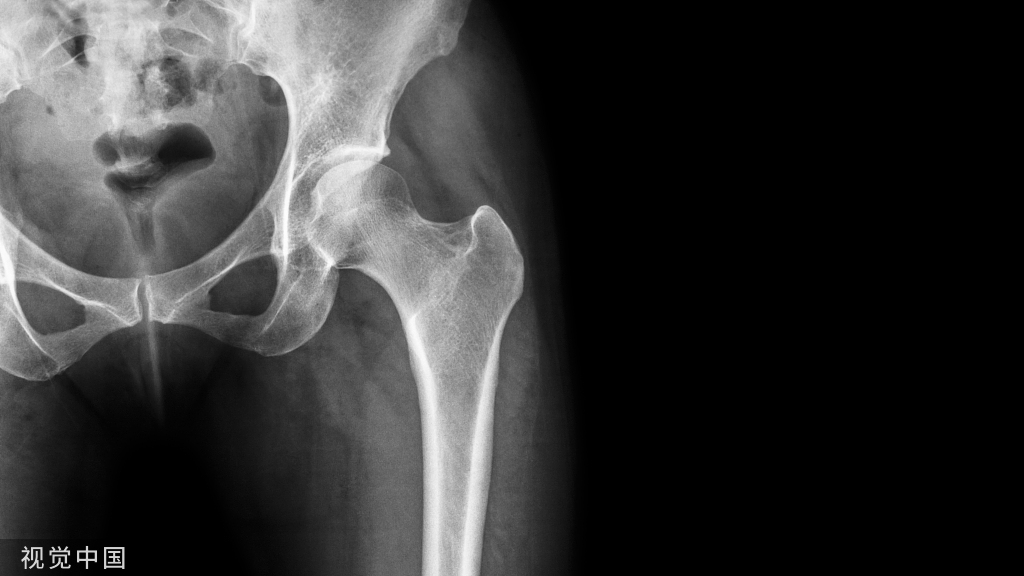

31、股骨颈环状透亮区

• 股骨颈环状透亮区,边缘硬化,是滑膜疝入骨皮质形成的皮质小坑。

• 皮质小坑之二: